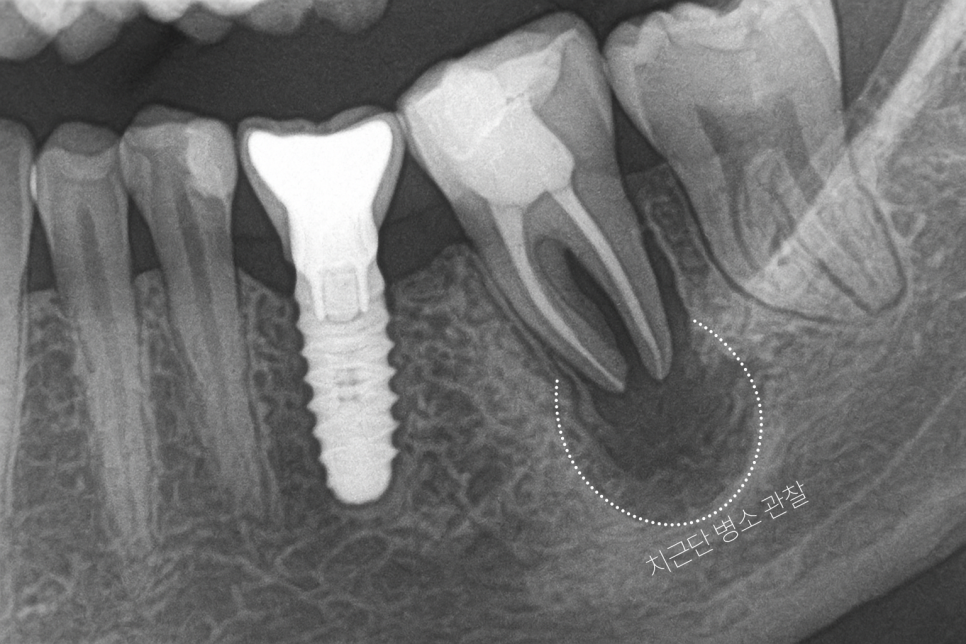

구강 및 방사선 검사를 진행합니다.

이렇게 촬영된 엑스레이를 기반으로

어떤 방향으로 진료하는 것이 좋을지를

결정합니다.

위 사진은

좌측 아래 첫 번째 큰 어금니 사진으로,

과거에 신경치료를 진행했던 흔적이

남아있습니다.

이를 통해 치근단 병소가 확인되어

재감염이 최종 확인되었습니다.

다행히도 치주 인대와 잔존 뼈의 건강 상태가

양호한 편에 속해 재식을 진행하기로

결정하였습니다.